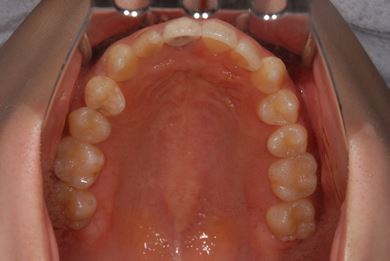

| 性別/年齢 | 女性 / 21歳 | ||||||||||||||||||||||||||||||||

| 主訴 | 歯の変色、欠けた部分を治したい。 | ||||||||||||||||||||||||||||||||

| 治療方針 | 上前歯を根管治療後、オールセラミッククラウンにて審美的回復を行う。 | ||||||||||||||||||||||||||||||||

| 治療内容 | オールセラミッククラウン2本(オールセラミック用土台2本) | ||||||||||||||||||||||||||||||||